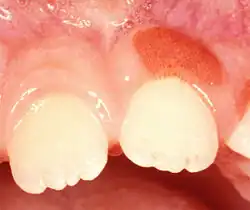

| Plasma cell gingivitis in an adult (histologically verified). |

Plasma cell gingivitis[1][2] is a rare condition,[3] appearing as generalized erythema (redness) and edema (swelling) of the attached gingiva, occasionally accompanied by cheilitis (lip swelling) or glossitis (tongue swelling).[4] It is called plasma cell gingivitis where the gingiva (gums) are involved,[5] plasma cell cheilitis,[5] where the lips are involved, and other terms such as plasma cell orifacial mucositis,[5] or plasma cell gingivostomatitis where several sites in the mouth are involved. On the lips, the condition appears as sharply outlined, infiltrated, dark red plaque with a lacquer-like glazing of the surface of the involved oral area.[5]

Plasma cell gingivitis appears as mild gingival enlargement and may extend from the free marginal gingiva on to the attached gingiva.[6] Sometimes it is blended with a marginal, plaque induced gingivitis, or it does not involve the free marginal gingiva. It may also be found as a solitude red area within the attached gingiva (pictures). In some cases the healing of a plaque-induced gingivitis or a periodontitis resolves a plasma cell gingivitis situated a few mm from the earlier plaque-infected marginal gingiva. In case of one or few solitary areas of plasma cell gingivitis, no symptoms are reported from the patient. Most often solitary entities are therefore found by the dentist.[2]

The gums are red, friable, or sometimes granular, and sometimes bleed easily if traumatised.[6] The normal stippling is lost.[7] There is not usually any loss of periodontal attachment.[6] In a few cases a sore mouth can develop, and if so pain is sometimes made worse by toothpastes, or hot or spicy food.[7] The lesions can extend to involve the palate.[7]